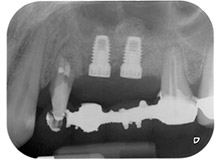

Figures 17 and 18 show the clinical result two months after the surgery. Tooth 24 exhibited reduced mobility of Miller class 1, and the soft tissues were free of inflammation. Probing was avoided at this point of time to prevent reinfection and to avoid violating the epithelial attachment. A control visit was scheduled for reentry and placement of healing abutments, six months after the insertion of the implants.

At the two-months recall, the mobility of the remaining “dental element” 24 was already reduced from Miller 2 to Miller 1. The soft tissue attachment was on the level of the neighbouring tooth 23. Moreover, there were no endodontic or periodontal symptoms, so its prognosis may have to be readjusted.

However, as most of the buccal and proximal bone is missing and the composite build-up extends to the apical section of the root, a higher reattachment level is not to be expected due to biologic reasons (Sculean et al., 2008).

The sinus floor and GBR procedures will likely result in an alveolar site able to support the implants and a good prognosis (Retzepi and Donus, 2010, Calin et al., 2014). After osseointegration, the implants at positions 25 and 26 will be restored with splinted crowns. If either of the teeth has to be extracted, it will be replaced with an implant-supported single crown.